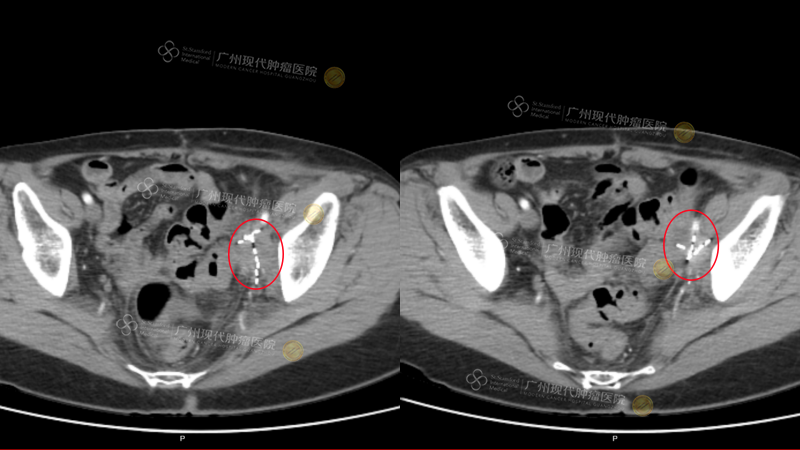

(该CT为9月22日于我院入院检查结果)

(盆腔:2次治疗后肿瘤缩小80%)(白色高亮为植入粒子)